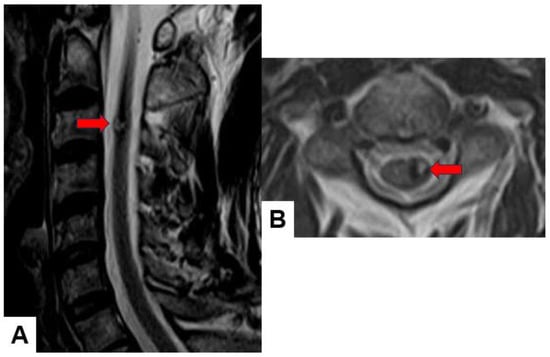

Ependymoma: Myxopapillary ependymomas typically present as well-defined intradural extramedullary masses with a heterogeneous signal intensity in T1-weighted images and hyperintensity in T2-weighted images (Figure 6). These tumors often demonstrate avid contrast enhancement.

Figure 6.

Thirty-seven M, spinal ependymoma, grade 1. (A) T1-weighted midsagittal image, (B) T1-weighted axial image at C4/5, (C) T2-weighted midsagittal image, (D) T2-weighted axial image at C4/5, (E) enhanced T1-weighted midsagittal image, and (F) enhanced T1-weighted axial image at C4/5. Red arrows indicate tumor; blue arrow shows enhancement. Green arrows indicate large syringomyelia.

Hemangioblastoma: Hemangioblastomas usually appear as well-circumscribed intramedullary lesions with marked hypointensity in T1-weighted images and hyperintensity in T2-weighted images due to the presence of cystic components and vascularity. They typically demonstrate avid contrast enhancement (Figure 7).